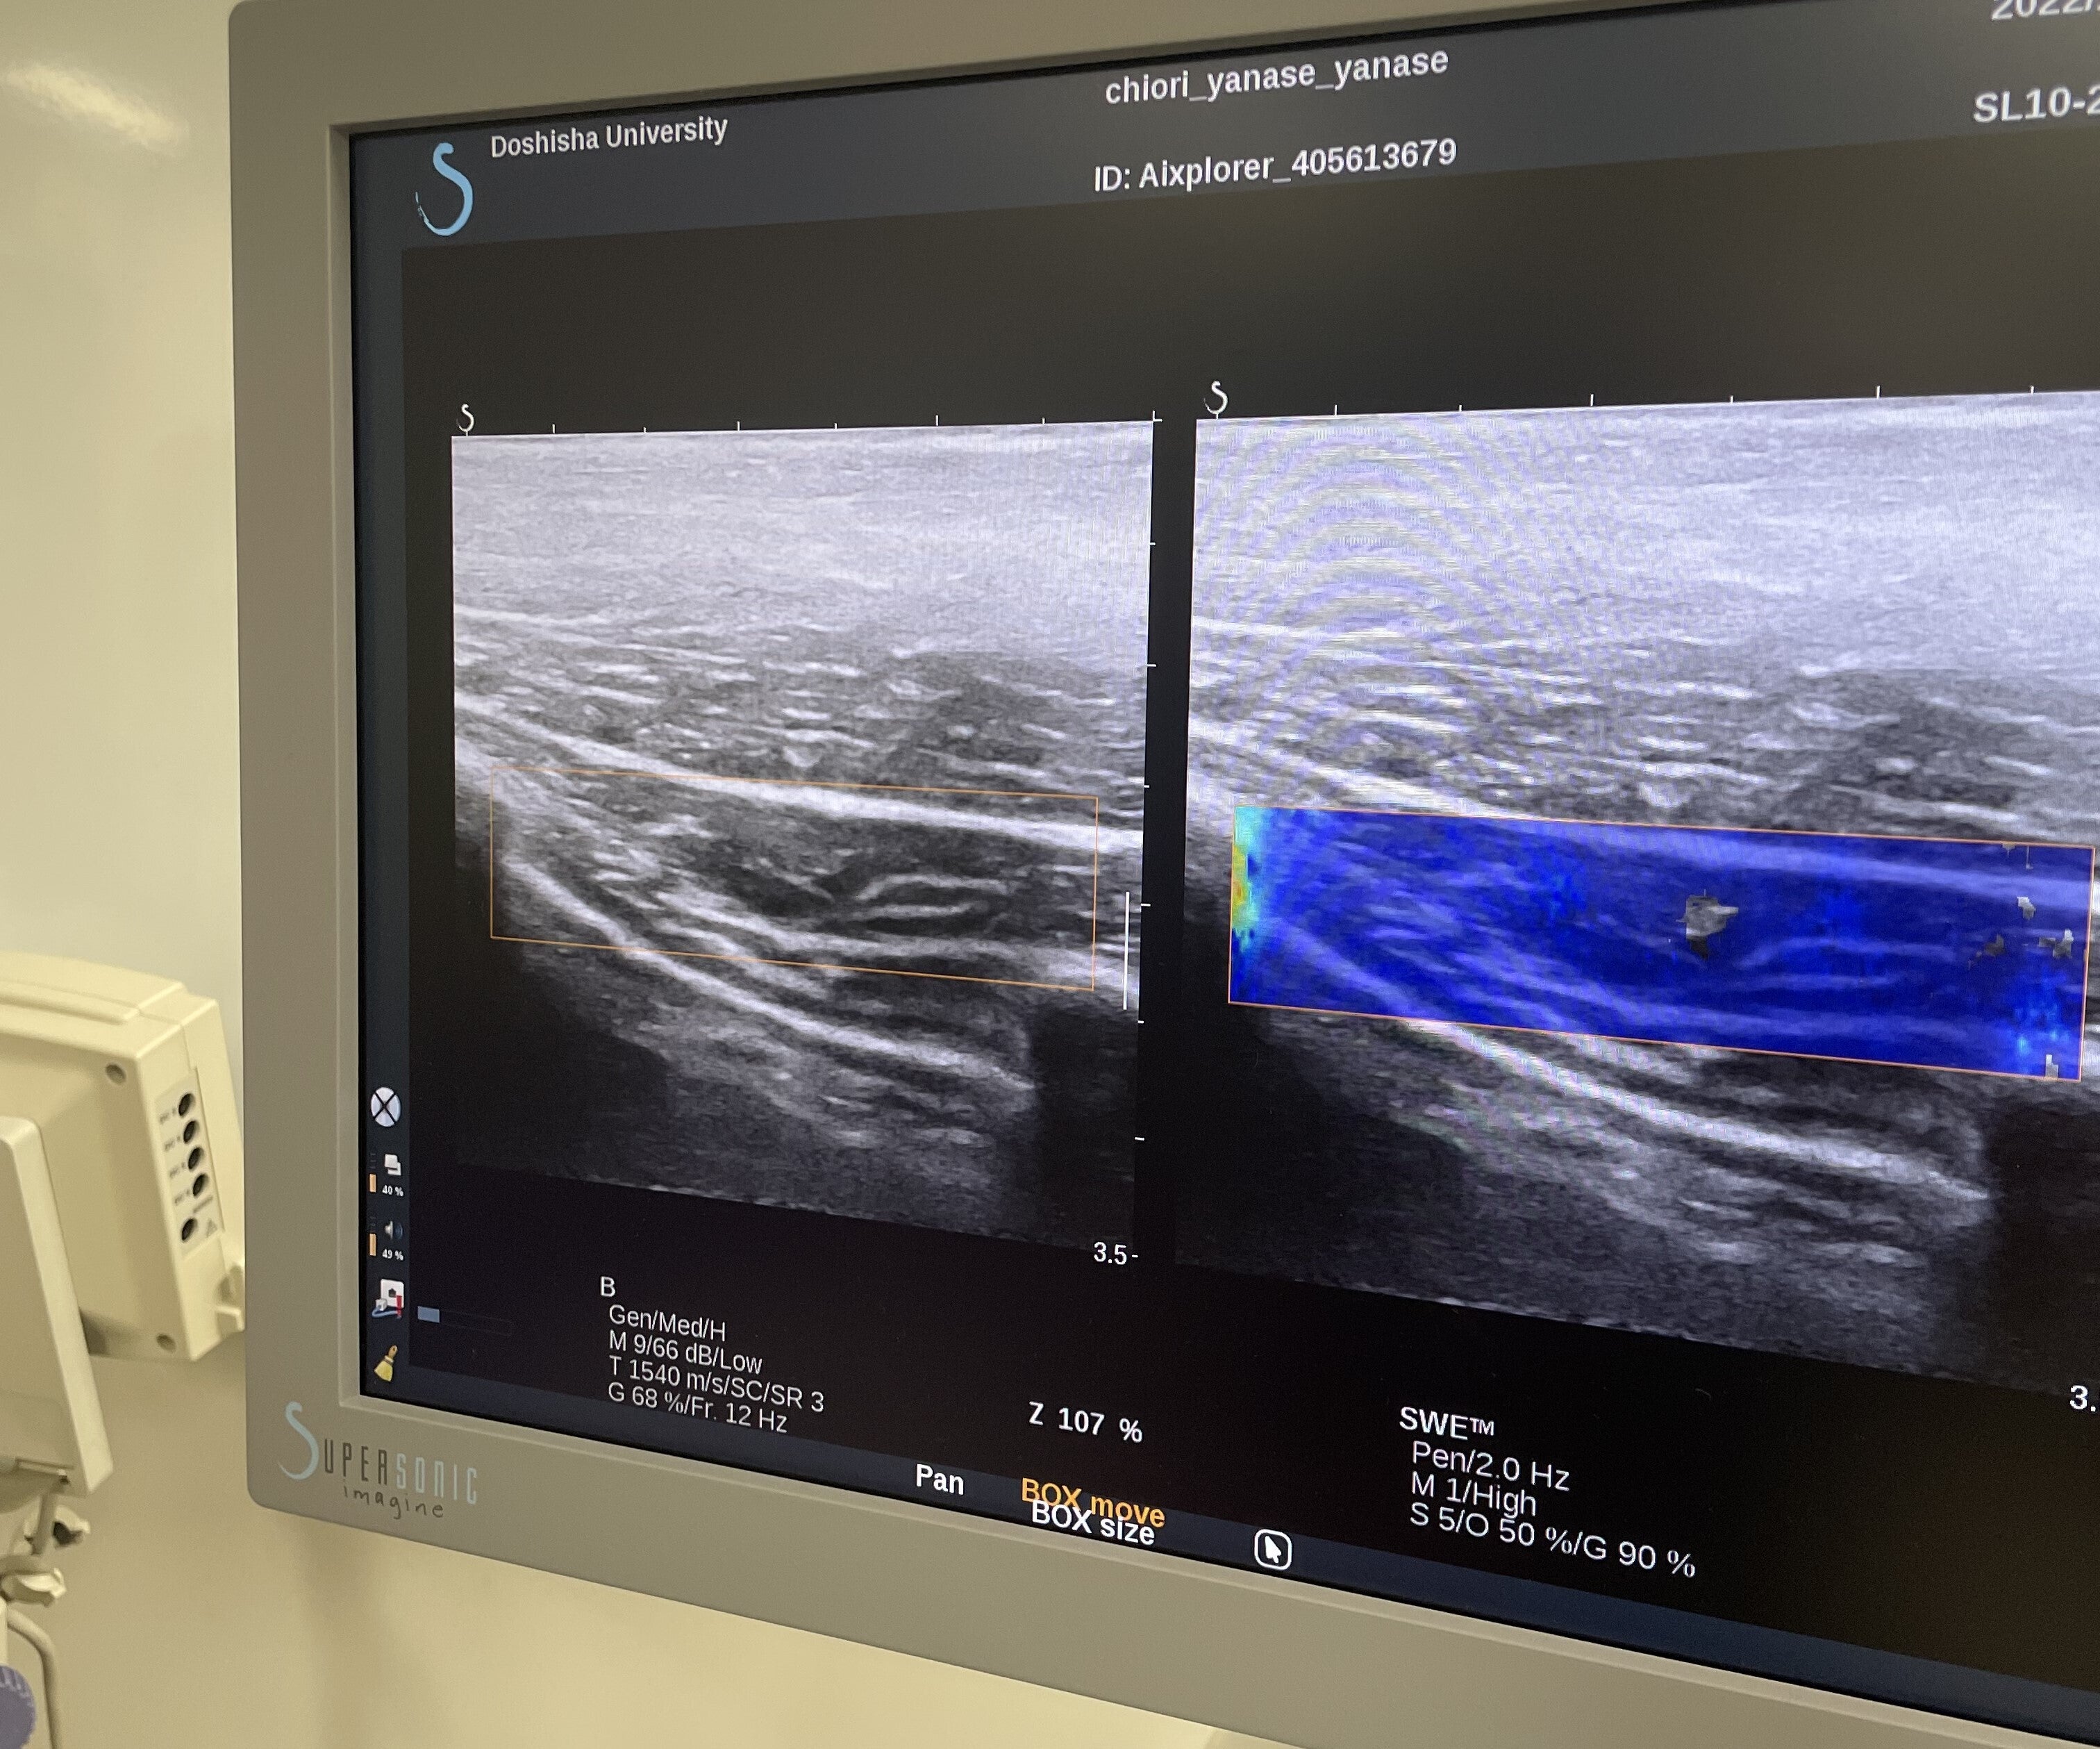

健康な大学生27名を集め、筋肉の硬さを測定することができる機械(超音波エラストグラフィ)を使い、胸の前にある筋肉(小胸筋)と背中にある筋肉(僧帽筋)の硬さを計測しました。さらに、背骨の歪みを計測できる機械(スパイナルマウス)を使い、猫背の程度を計測しました。そして、各筋肉の硬さと猫背の関係を調べました。

超音波エラストグラフィの画像

筋肉の硬さを計測できる装置を使って研究しました。